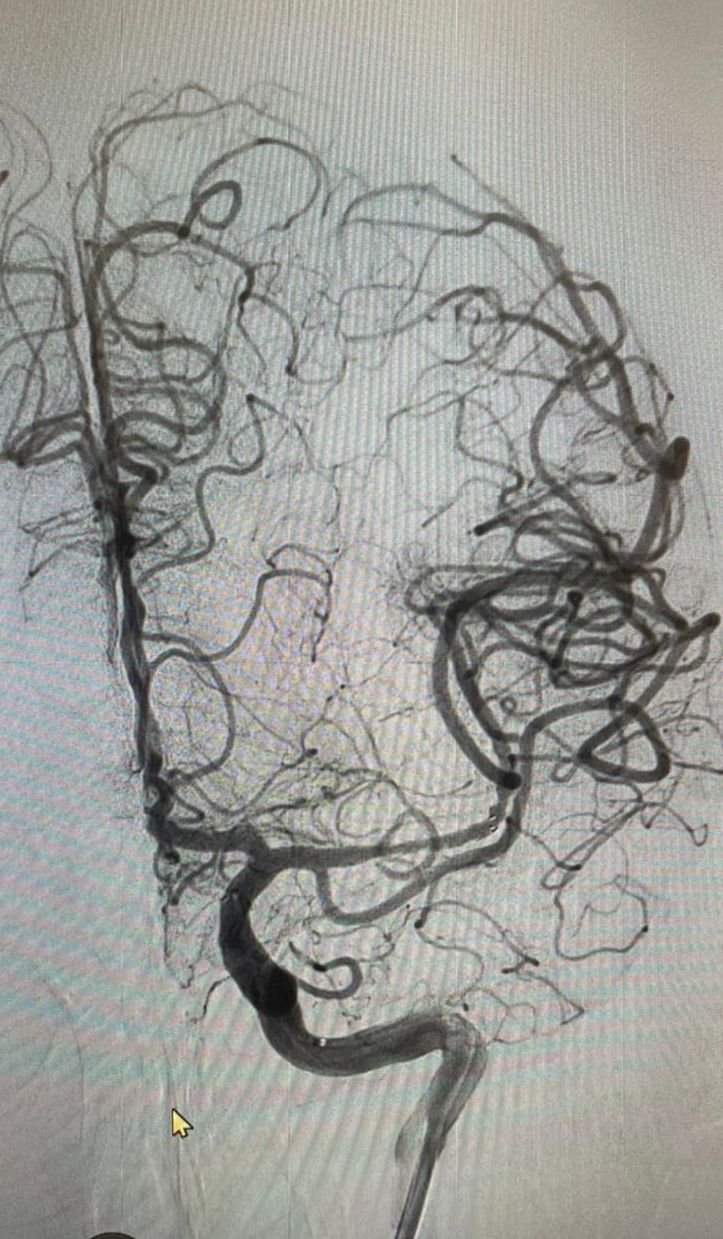

Pensiones Civiles del Estado (PCE) realiza cirugía de rescate cerebral vascular a derechohabiente femenina de 72 años de edad que presentó una embolia cerebral.

La cirugía fue realizada por el médico especialista de Pensiones Civiles, Alejandro Rodríguez Orozco, radiólogo neuro intervencionista, junto con el equipo de hemodinamia del Hospital Ángeles Chihuahua.

La paciente con antecedente de arterioesclerosis y lesiones en las carótidas, perdió la fuerza de forma súbita en la mitad de su cuerpo, afasia, pérdida del lenguaje y parálisis facial, por ello, se le realizó una resonancia magnética, en la que se detectó la obstrucción de una arteria por un coágulo, identificando la zona afectada y se hizo el rescate, que consiste en introducir catéteres desde la ingle hasta el cerebro.

Con este procedimiento, la derechohabiente, ha recuperado la circulación sanguínea hacia el cerebro, el lenguaje y el movimiento se irá recuperando paulatinamente conforme se progrese con las sesiones de fisiatría, tratamiento farmacológico y cambios en el estilo de vida.